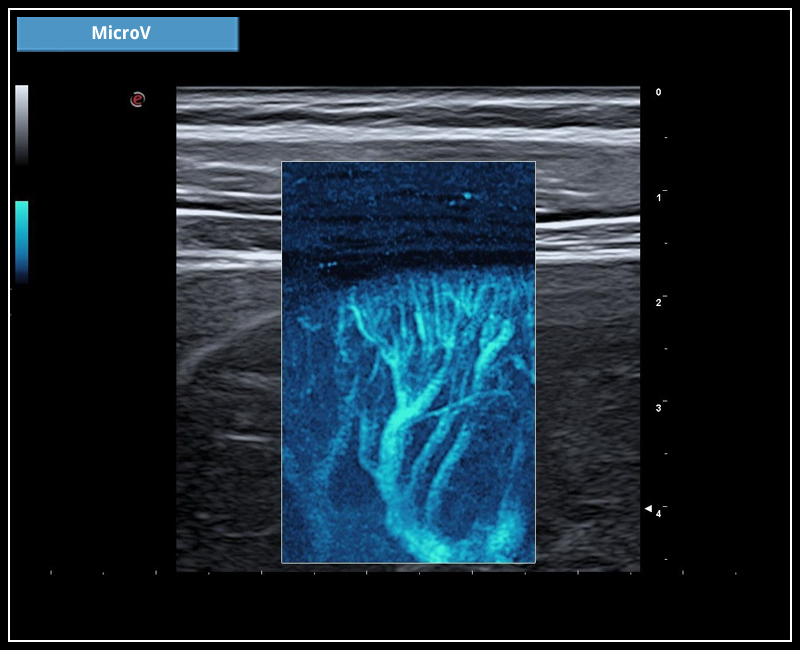

- Supersentiv Doppler og Micro-V

Ny bildeoptimaliseringsteknologi; X-View 5.0, fremhever hver eneste piksel, fjerner støy i bildet og forsterker overganger mellom strukturer. Dette gir en utrolig skarphet i bildet og hjelper deg å se hver eneste detalj. M-View 5.0 styrer signalene i flere retninger og legger informasjonen til bildet. Denne utrolige effekten reduserer artefakter og støy i tillegg til å forsterke bildeklarheten. Esaote er kjent for en ekstremt følsom farge – og powerdoppler og leveres nå i tillegg med MicroV. Alle modaliteter kan man styre signalet i ønsket retning, farge og følsomhet. Velg ønsket modul og du vil se mye der du tidligere ikke fikk frem dopplerinformasjon.

Ny doppler teknologi: MicroV.

MicroV, den nyeste dopplerteknologien fra Esaote med en enestående følsomhet selv i små kar og deteksjon av lave hastigheter. MicroV har en algoritme som helt overlegent separerer bevegelse av væske fra andre bevegelser som skaper forstyrrelser. Dette gir en helt unik dopplerfølsomhet ikke sett tidligere. Med MicroV er det mulig å endre visualiserings algoritmen for å ytterligere forsterke det du ønsker å se.